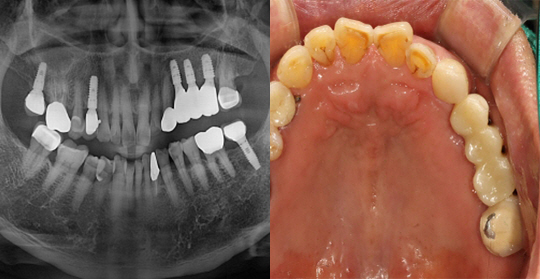

(50세 남 환자)